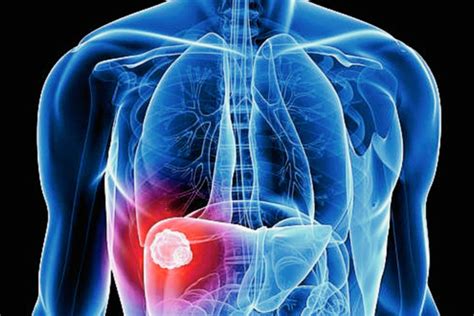

Tudo o que você precisa saber sobre a vesícula biliar - Cirurgião | Dr

WebLas vesículas también pueden ser formaciones anormales como las vesículas cutáneas, las lesiones que se parecen a pequeños levantamientos de la piel que contienen. WebEl doctor me hizo prueba de sangre y me dijo que si estaba embarazada y que todo normal, me hizo una eco pero dijo que era muy pronto para ver algo y me dejo. WebEn el seguimiento médico del embarazo, la vesícula vitelina puede servir, junto a otros elementos e indicadores, como marcador de la correcta evolución del. WebSe examinarán los ganglios linfáticos sobre la clavícula y los ganglios linfáticos de otras partes. Si los síntomas y/o los resultados del examen físico sugieren que usted podría. WebMarta Marnet 47.514. 3 feb 2019 a las 14:32. Hola, Esta estructura embrionaria puede verse en una ecografía vaginal desde la semana 5º de embarazo y, de hecho, es muy. WebHola, Buenos días mi pregunta es la siguiente el día 2 de octubre fue mi último día de la regla después de todo confirmado que me encuentro embarazada, pero. WebSi hay vesícula vitelina es buena señal; Si hay saco vitelino es buena señal - Mejores respuestas; Si hay vesícula vitelina hay embrión - Mejores respuestas; Saco gestacional. WebEn la mayoría de los casos, la limpieza de la vesícula implica comer o tomar una combinación de aceite de oliva, hierbas, y algún tipo de jugo de fruta durante.